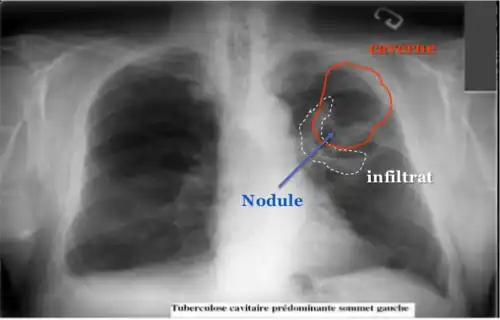

La modalité de diagnostic radiologique se révèle très utile et indiquée comme étant un examen de première intention en cas de tuberculose pulmonaire et ostéoarticulaire[78]. Cela est justifié par les images radiologiques plus ou moins spécifiques à la tuberculose. La littérature rapporte que la spécificité varie de 27 à 81 % selon l’étude. Les imageries idéales et révélatrices de la tuberculose répondent à certains attributs dont le premier est lié au siège. En raison de l’affinité que les BK ont envers les régions aérées, la lésion radiologique est souvent observée dans les parties hautes des poumons. Néanmoins, l’image radiographique peut contenir différentes formes :

- infiltrat : traduisant des lésions débutantes de l’infection via une opacité peu dense, hétérogène et étendue ;

- nodule : granulome de taille variable, isolé ou groupé ;

- tuberculome : nodule isolé pseudotumoral ;

- caverne : excavation par perte de substance au sein d’un infiltrat, aux parois épaisses.